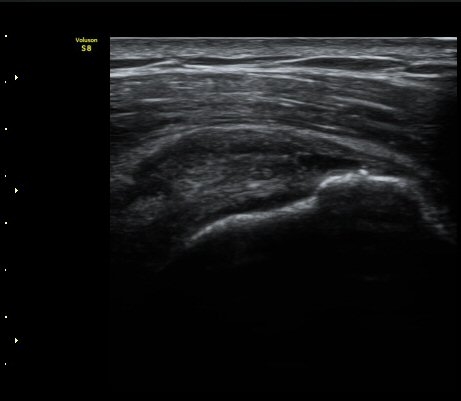

±Ø»ó°Ç³»Ãø Á¾´Ü¸é°Ë»ç¿¡¼­ ±Ø»ê°Ç ºÎÂøºÎÀÇ  ÀÛÀº ÆÄ¿­°ú Á¡¾×³¶ ºÎÁ¾ÀÌ °üÂûµÊ(±×¸² 2, 3).

±Ø»ó°Ç ¿ÜÃø Á¾´Ü¸é°Ë»ç ½Ã Á¡¾×³¶ ºÎÁ¾ÀÌ °üÂûµÊ(±×¸² 4).

±Ø»ó°Ç ±ÙÀ§ºÎ ±Ø»ó°Ç ³»ÃøÀÇ Àú¿¡ÄÚ ºÎÁ¾°ú Á¡¾×³¶ ºÎÁ¾ÀÌ °üÂûµÊ(±×¸² 5).

±Ø»ó°Ç ¿øÀ§ºÎ ±Ø»ó°Ç ºÎÂøºÎ ÀÛÀº ÆÄ¿­ÀÌ °üÂûµÊ(±×¸² 6).